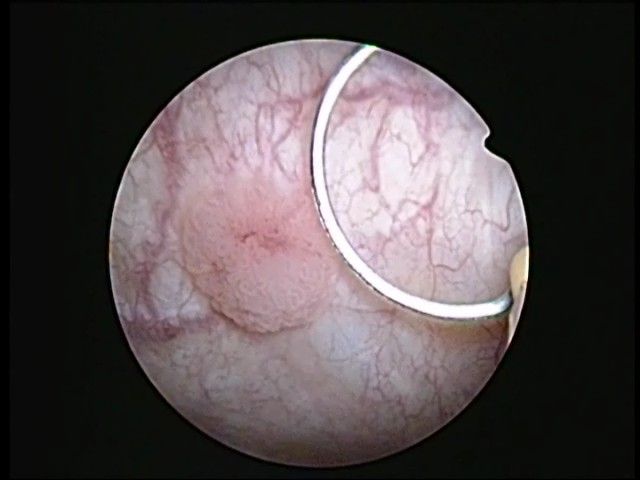

Mr Mor lio 022 0002cancer de vessie superficiel vu en cystoscopie en lumière blanche

Un polype est un cancer de vessie (preuve apportée par l’analyse anatomopathologique) sauf très rares cas.

Ce polype est soit SUPERFICIEL = n’envahit pas le muscle vésical, soit PROFOND = envahit le muscle vésical.

Pour les polypes superficiels, la résection transuréthrale de vessie ou RTUV permet l’exérèse du polype